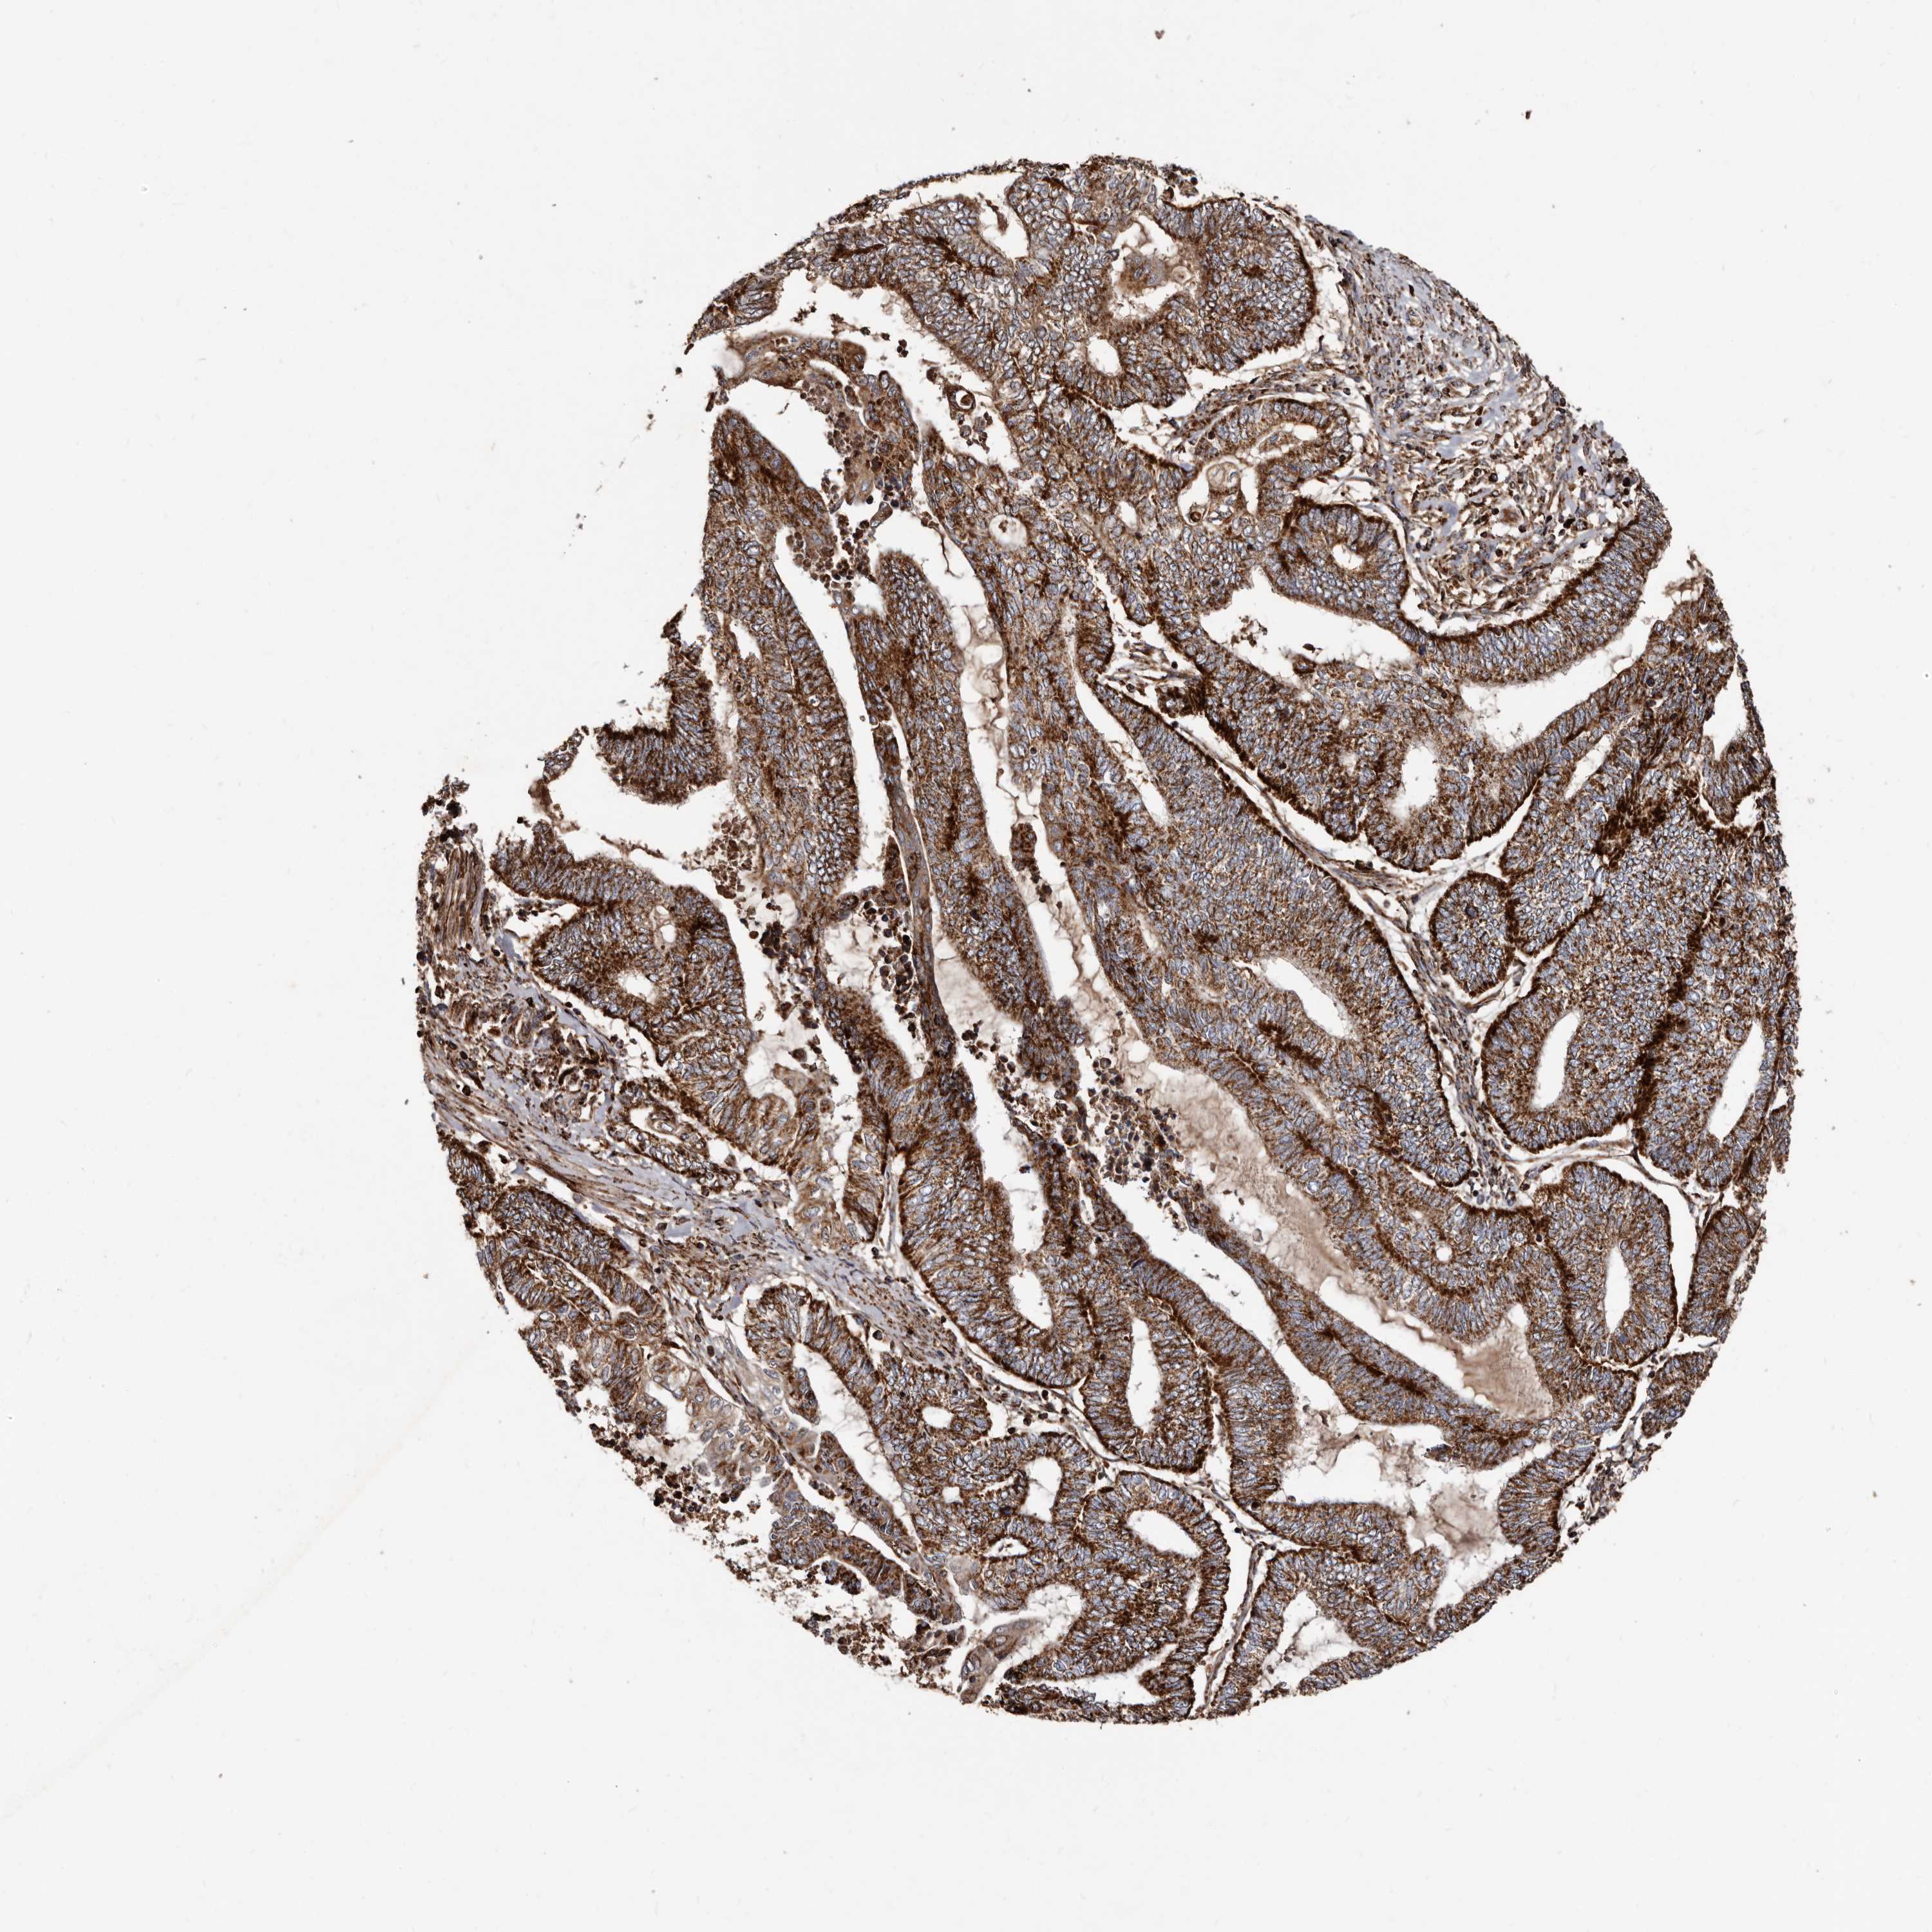

ENDOMETRIAL CANCER - Protein expressioni

A mouse-over function shows sample information and annotation data. Click on an image to view it in a full screen mode. Samples can be filtered based on level of antibody staining by selecting one or several of the following categories: high, medium, low and not detected. The assay and annotation is described here.

Note that samples used for immunohistochemistry by the Human Protein Atlas do not correspond to samples in the TCGA dataset.

Antibody stainingi

Antibody staining in the annotated cell types in the current human tissue is reported as not detected, low, medium, or high, based on conventional immunohistochemistry profiling in selected tissues. This score is based on the combination of the staining intensity and fraction of stained cells.

Each image is clickable and will lead to virtual microscopy that enables deeper exploration of all samples and also displays staining intensity scores, fraction scores and subcellular localization as well as patient and tissue information for each sample.

Antibody HPA027878

Antibody CAB004206

Staining

High

Medium

Low

Not detected

Intensity

Strong

Moderate

Weak

Negative

Quantity

>75%

75%-25%

<25%

None

Location

Nuclear

Cytoplasmic/membranous

Cytoplasmic/membranous,nuclear

Adenocarcinoma, NOS

Adenocarcinoma, metastatic, NOS

Neoplasm, malignant, NOS